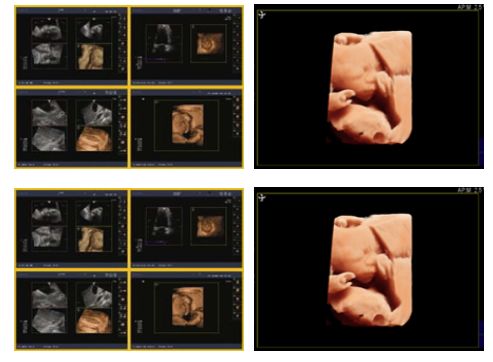

是目前最先进的专业三维成像技术,它避免了重建三维成像对医生手法及经验的过度依赖,可实时监控成像质量。适用范围广泛,可用于小器官如乳腺、妇科、产科、常规腹部等脏器,提供更高的三维处理速度以及真实的三维图像,实时状态下提供流畅的三维动态图像;三维图像可任意旋转、切割和测量。

它避免了重建三维成像对医生手法及经验的过度依赖,可实时监控成像质量。适用范围广泛,可用于小器官如乳腺、妇科、产科、常规腹部等脏器,提供更高的三维处理速度以及真实的三维图像,实时状态下提供流畅的三维动态图像;三维图像可任意旋转、切割和测量。